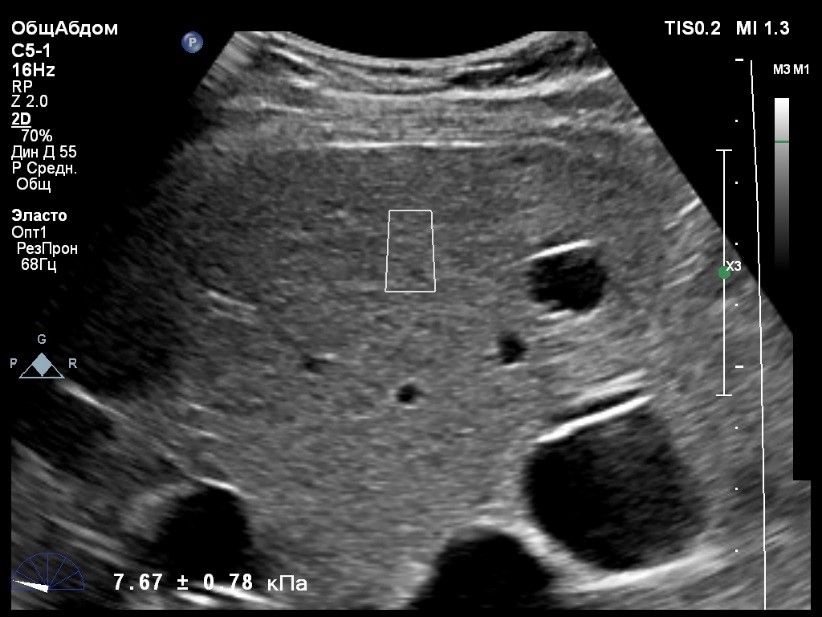

Пациент обратился к доктору с направлением на исследование степени жесткости печени в июне 2017 года. Из истории болезни, пациент страдает Гепатитом С с 2015 года. Лечение не получал. В апреле 2016 года, с помощью транзиентной эластографии была установлена медиана жесткости печени 5,8 kPA (4,4-7,7). На момент настоящего исследования, пациент не принимал пищу на протяжении 4 часов, АСТ, АЛТ не превышают патологических значений. Для оценки жесткости была выбрана технология компании Philips ElastPQ (точечная эластография) и прибор компании Philips Epiq 7 Исследование было проведено в соответствии с клиническими рекомендациями для ультразвуковых приборов компании Philips. В результате исследования были получены следующие результаты:

| 1 [4.94] kPa | 2 [7.09] kPa | 3 [7.13] kPa |

| 4 [4.74] kPa | 5 [5.17] kPa | 6 [7.78] kPa |

| 7 [6.19] kPa | 8 [7.63] kPa | 9 [4.64] kPa |

| 10 [6.18] kPa | 11 [4.49] kPa | 12 [4.54] kPa |

| 13 [6.08] kPa | | |

Стандартное Отклонение [1.17] kPa Медиана Жесткости [6.08] kPa Фактор Качества IQR/Med 9%

Зона интереса расположена на более чем на один сантиметр глубже капсулы, параллельно ходу луча, в середине изображения, в участке печени лишенном артефактов.

Капсула видна как белая линия перпендикулярная ходу ультразвукового луча, исследования производятся приблизительно в одном и том же сегменте печени.

Стандартное отклонение (0,96 kPA) не превышает 30 процентов от полученного значения (4,54 kPA).

Зона интереса расположена вне крупных сосудов.

Для интерпретации полученных клинических данных были использованы Рекомендации по проведению эластографии сдвиговой волной для оценки жесткости печени при использовании ультразвуковых аппаратов компании Филипс с примером протокола. Анамнез основного заболевания пациента достаточно короткий и показатели жесткости печени, полученные в 2016 свидетельствуют об отсутствии значимых фиброзных изменений. Однако, в течении всего времени пациент не получал специфического лечения. Данный факт является показанием для динамического наблюдения и оценки жесткости печени. Подготовка пациента соответствовала проводимому исследованию. Представленные слайды проведенного исследования свидетельствуют о правильном техническом исполнении проб, что позволяет заключиться о достоверности полученных измерений. Таким образом, учитывая полученную медиану жесткости на уровне 6.08 кРа (4.49 – 7.78 kPa) и уровень стандартных отклонений не превышающих 30%, полагаю, что уровень степени фиброза соответствует стадии F 0-1. Заведующий отделением УЗД МЦ «Асклепий», Глушенко Д. Е.